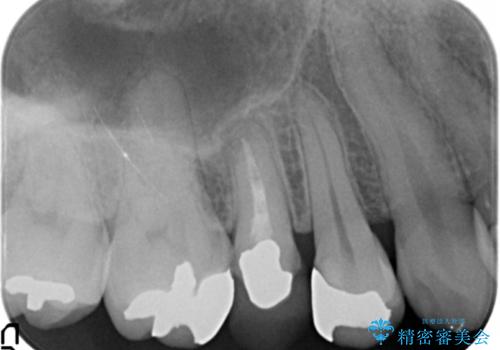

精査したところ、右上の奥歯(右上5)に根尖病変を認めたため、こちらは根管治療後にセラミッククラウンによる補綴を行いました。